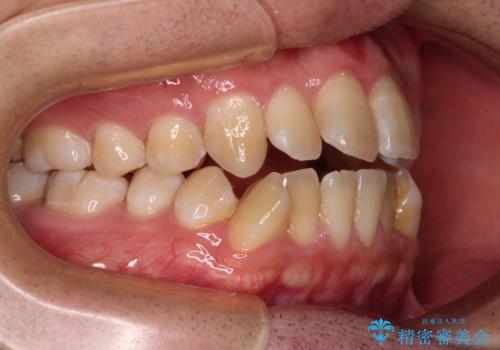

オープンバイトをインビザラインで矯正治療

- 前歯の開咬を気にして来院された患者様です。

開咬の治療は、前歯を閉じるように動かすとともに、上下臼歯を圧下(骨内にめり込ませる)させることで進めて行きます。

インビザラインは臼歯の圧下を効果的に行えるため、インビザラインを用いて矯正治療を行うこととしました。